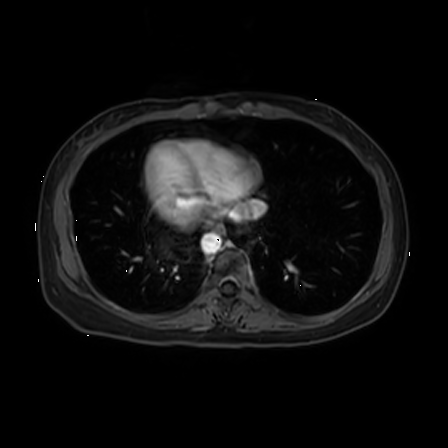

Qualitative evaluation.

To provide a more intuitive observation of our medical vision generalist, we provide the visualization of different tasks in Figure 4.